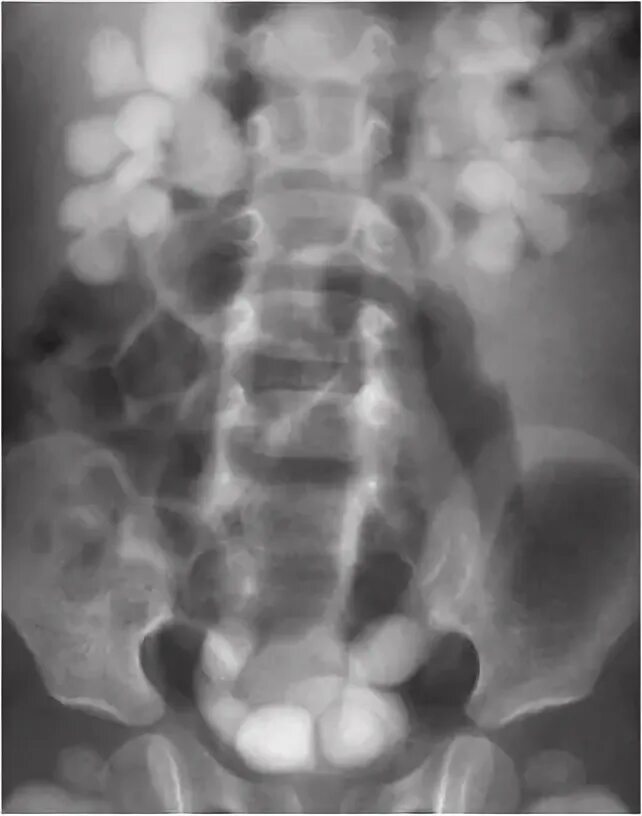

Мегауретер у детей что это